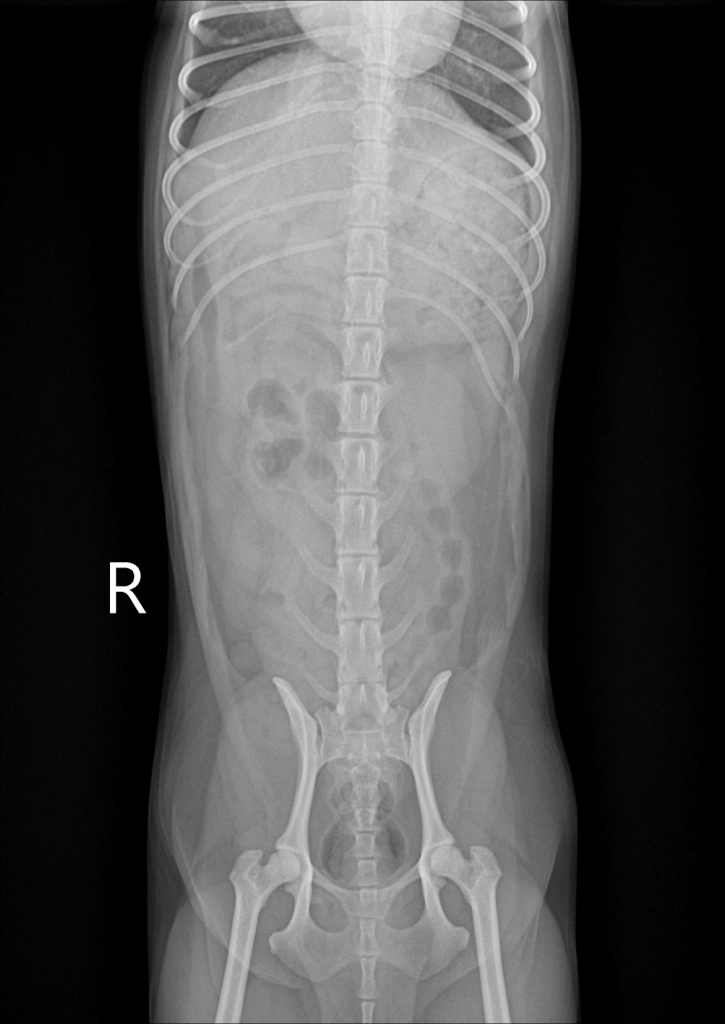

우리 강아지 디스크 일까요..?움직이지 않아요

평소랑 달리 움직이없고 헥헥 거리며 끙끙 앓아요 사진상으로 디스크 의심갈만한 문제가 없어보인다는데 전문가들의 의견이 궁금합니다 ㅜ ㅜ

방사선 만으로는 디스크를 확진할 수 없습니다.

그외 신경검사인 심부통증 반응과 자세반응 등 신경계 검사와 확진을 위해서는 CT촬영과 MRI 촬영이 필요합니다.

화살표를 해둔 부분의 디스크 공간이 좁아 보이는 양상이 경미하게 관찰되어 의심해볼만한 가능성은 있으나 디스크는 엑스레이 사진으로 진단되는 질환이 아니기에 다른 검사 결과에서 디스크를 강력히 의심할만하다면 MRI 검사가 추천됩니다.

반복된 촬영에서 재현성도 확보되어 증상이 지속된다면 이 사진을 근거로 MRI 촬영을 해봐야 하는 사항으로 판단됩니다.